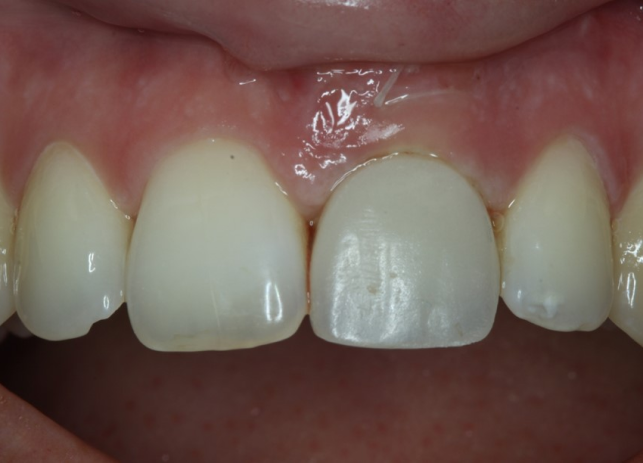

Рис. 9 и 10 после начального заживления временная коронка была адаптирована с помощью композита для тренировки и формирования мягких тканей, аналогично прилегающему правому центральному резцу. Нашей целью также было добиться одинаковой длины 11 и 21 зубов или выровнять высоту десны